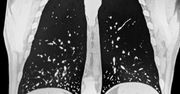

Histoplazmoza (choroba Darlinga) - objawy, przyczyny, leczenie